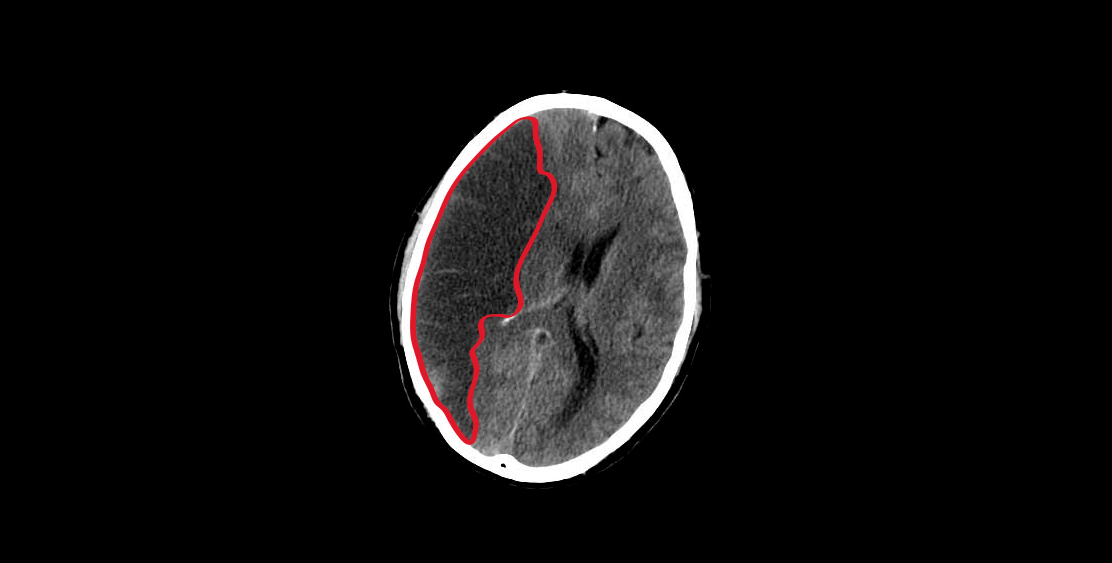

(s. a.) (s. f.). [Entrada: Brain isquemia] [tomografía axial computarizada]. Tomada de https://en.wikipedia.org/wiki/Brain_ischemia

Las arterias vertebrales se fusionan intracranealmente formando un tronco conocido como arteria basilar. En la siguiente imagen puedes observar el énfasis en las regiones que irriga el sistema carotídeo y vertebrobasilar:

Corte transversal de cerebro humano, el circuito cerebral arterial y sus principales áreas de irrigación

(s. a.) (s. f.). [Entrada: Edema cerebral] [tomografía]. Tomada de https://commons.wikimedia.org/wiki/File:MRI_brain_tumor.jp